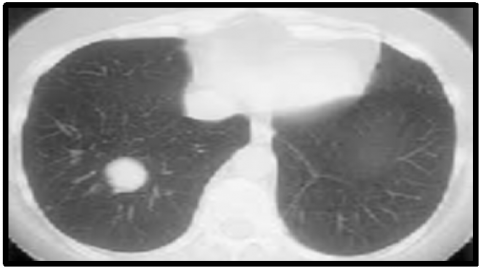

The ELCAP [23] and LIDC benchmark datasets [24, 25] are used to assess how well the suggested method performs in lung nodule identification. The DIOCOM format is used to store lung CT images, and each scan has 512 pixels in width and 512 pixels in height. Figure 5 displays the image of a human lung with a tumor that is used as the input image. The input image is clustered using the FCM technique and then the clustered output is segmented into the tumor region using the histogram approach. The FCM algorithm takes less time to execute than the FLICM and KWFLICM algorithms, but it is unable to cluster images with outliers or noise like salt and pepper. The FCM clustering and segmentation image is displayed in Figure 6. Given an input image, the FLICM algorithm is utilized to do the clustering. The tumor zone is divided from the FLICM algorithm's clustered output using the histogram approach. While the FLICM approach takes longer to execute than the other two, it produces better clustering results when compared to FCM in cases where the image contains outliers or salt and pepper noise. Figure 7 shows the FLICM segmentation and clustering image.

(a)

(b)

Figure 7. (a) FLICM output; (b) segmented image